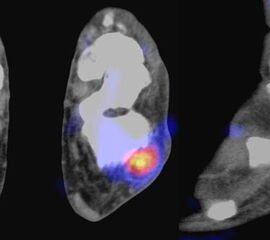

Abbildung 2.3.

Klärung bei Schmerzen im rechten OSG bei OCL an der medialen Talusschulter. Z. n. OSG-Distorsion vor 2 Jahren und Z. n. OSG-Fraktur / Syndesomosenruptur. Ausgedehnte OCL, hier jedoch kein erhöhter Knochenmetabolismus; lediglich Nachweis einer Stressreaktion im Bereich der Synchondrose eines Os trigonum als Schmerzursache.

Zum Lesen der Bildbeschreibung und zur Vollansicht bitte das Bild anklicken. Bild: H. C. Rischke